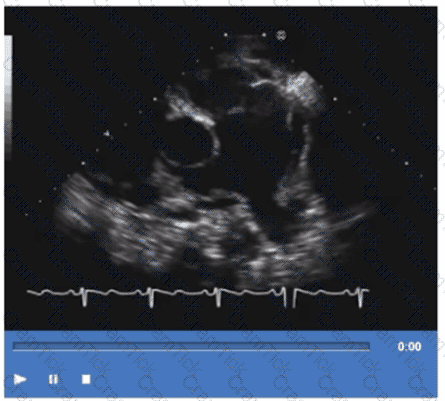

Which step is next in further evaluation of the abnormality shown in this video?

Which is the most likely abnormality represented in these images from a 48-year-old man with shortness of breath?